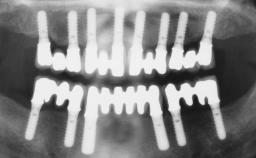

A fully edentulous 65-year-old woman was referred to our clinic for esthetic and functional dental rehabilitation. The patient presented with inadequate complete maxillary and mandibular prostheses, insufficient vertical dimension, and extensive tooth wear. The clinical examination and anamnesis showed no local or systemic contraindications, no signs or symptoms of bruxism, and an absence of smoking habits. The treatment proposed was implant placement in the mandibular interforaminal area and immediate loading with a fixed definitive prosthesis. A removable mucosa-supported complete prosthesis was indicated for the upper jaw, since its bone structure offered satisfactory retention and the financial condition of the patient disfavored a full-mouth implant-supported rehabilitation.

# of Implants 4

Type of Implants One-Piece

Attachment One-Piece